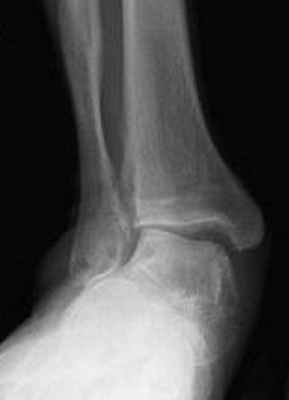

В первую очередь показано выполнение рентгенографии с нагрузкой в прямой и боковой проекции. При этом в прямой проекции выявляется неполное покрытие суставной поверхности головки таранной кости ладьевидной костью, увеличенный угол между таранной костью и первой плюсневой костью (угол Simmon), что встречается со 2 А стадии.

На боковых рентгенограммах определяется увеличенный таранно-плюсневый угол (угол Meary >4° свидетельствует о плоской стопе). Также снижается угол высоты пяточной кости (в норме 17-32°).

На 3-4 стадиях определяются признаки подтаранного артрита, на 4 стадии появляется картина подвывиха таранной кости в голеностопном суставе.